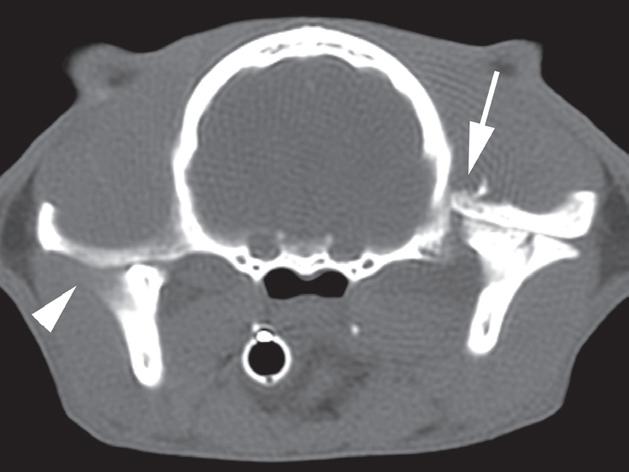

Rycina 5.6.6. Przysadkowozależna nadczynność kory nadnerczy (pies) TK

Badanie wykonano u 12-letniego, kastrowanego boston teriera z podejrzeniem przysadkowozależnej nadczynności kory nadnerczy. W badaniu natywnym oba nadnercza (a, b – strzałki) są powiększone i zaokrąglone, a także wykazują jednorodną densyjność tkanek miękkich. Widoczna jest mineralizacja ściany tętnicy krezkowej przedniej, która jest zmianą wtórną do zespołu Cushinga (b – gwiazdka). Obraz po podaniu dożylnego środka kontrastowego mózgowia ujawnia duży, intensywnie wzmacniający się rozrost przysadki (d – otwarta strzałka), przypuszczalnie o charakterze funkcjonalnym